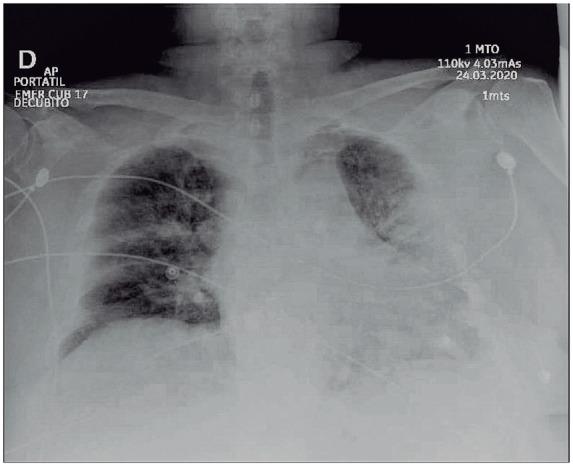

We present a case of a 69-year-old man with a clinical presentation of massive-like pulmonary embolism (PE) overlapping with severe COVID-19 pneumonia. The diagnosis was made based on hypotension, severe oxygen desaturation (33%), and right ventricular dysfunction (RVD). We used alteplase and low-molecular-weight heparin, obtaining immediate clinical improvement. Also, we identified an extremely elevated D-dimer (31.2 mcg/mL), and computed tomography pulmonary angiography (CTPA) revealed an unexpected low thrombus burden and a crazy-paving pattern. Considering this, we decided to discontinue the alteplase. Therefore, the mechanisms of pulmonary hypertension and RVD could be multifactorial. Despite the patient's respiratory status worsening and ongoing mechanical ventilation, biomarkers kept lowering to normal ranges. It appears a favourable outcome was related to early PE diagnosis and a multimodal therapeutic approach.